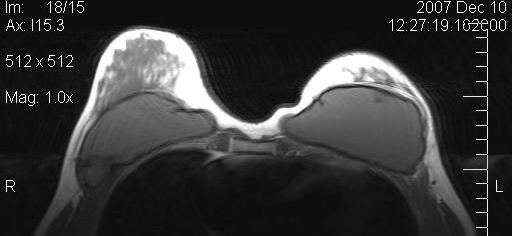

Figure 10 [Fig. 10] and Figure 11 [Fig. 11] show the MRIs of a patient pre- and postoperatively.

Figure 10: Preoperative MRI of a patient with capsular contracture

Magnetic resonance imaging (MRI) of the breasts was performed in 5 patients preoperatively and 6 months postoperatively. The evaluation by MRI based volumetry gave inconsistent results, presumably due to the fact that volume (the implant) is first removed, and then added by fat grafting in one procedure. Also, the form of the preoperatively often very tight breasts changed dramatically. All MRI showed massive increase in fat tissue. No cysts were observerd.